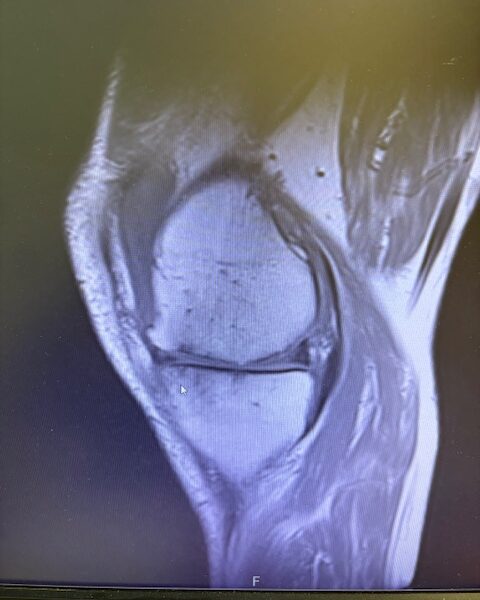

Ο ακτινολογικός έλεγχος (ακτινογραφίες/μαγνητική τομογραφία) ανέδειξε προχωρημένη οστεοαρθρίτιδα του έσω κονδύλου, με πλήρη διατήρηση του έξω διαμερίσματος και της επιγονατιδομηριαίας άρθρωσης. Με βάση αυτά τα ευρήματα, ο ασθενής ήταν ιδανικός υποψήφιος για μερική (μονοκονδυλική) αρθροπλαστική γόνατος.

Η επέμβαση πραγματοποιήθηκε με ελάχιστα επεμβατική προσπέλαση και τοποθέτηση πρόθεσης μόνο στον έσω μηροκνημιαίο διαμέρισμα του γόνατος.

Η ακριβής προσαρμογή του εμφυτεύματος επιβεβαιώθηκε διεγχειρητικά, εξασφαλίζοντας σταθερότητα και φυσική κίνηση της άρθρωσης.